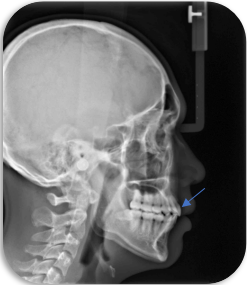

治疗前

拔牙治疗后

鼻唇角:鼻唇角越小,面型越突

当前牙后移,上唇随之后移,鼻唇角增大,突面型改善